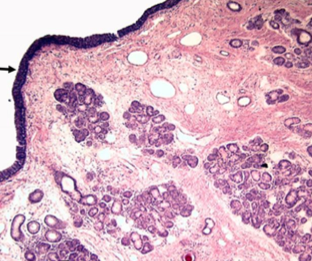

olfactory epithelium, which consists of__ and ____, and the bipolar neurons known as olfactory cells

basal cells, supporting cells

there is a lack of CILIA in ___ epithelium

olfactory

Bowman’s glands

produce proteinaceous serous secretions to clear cilia and facilitate access of new odorants.